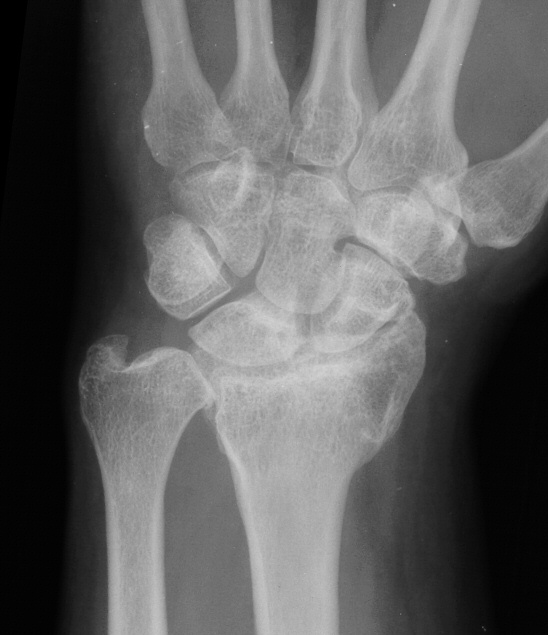

Preoperative Xrays:

Image Image Image